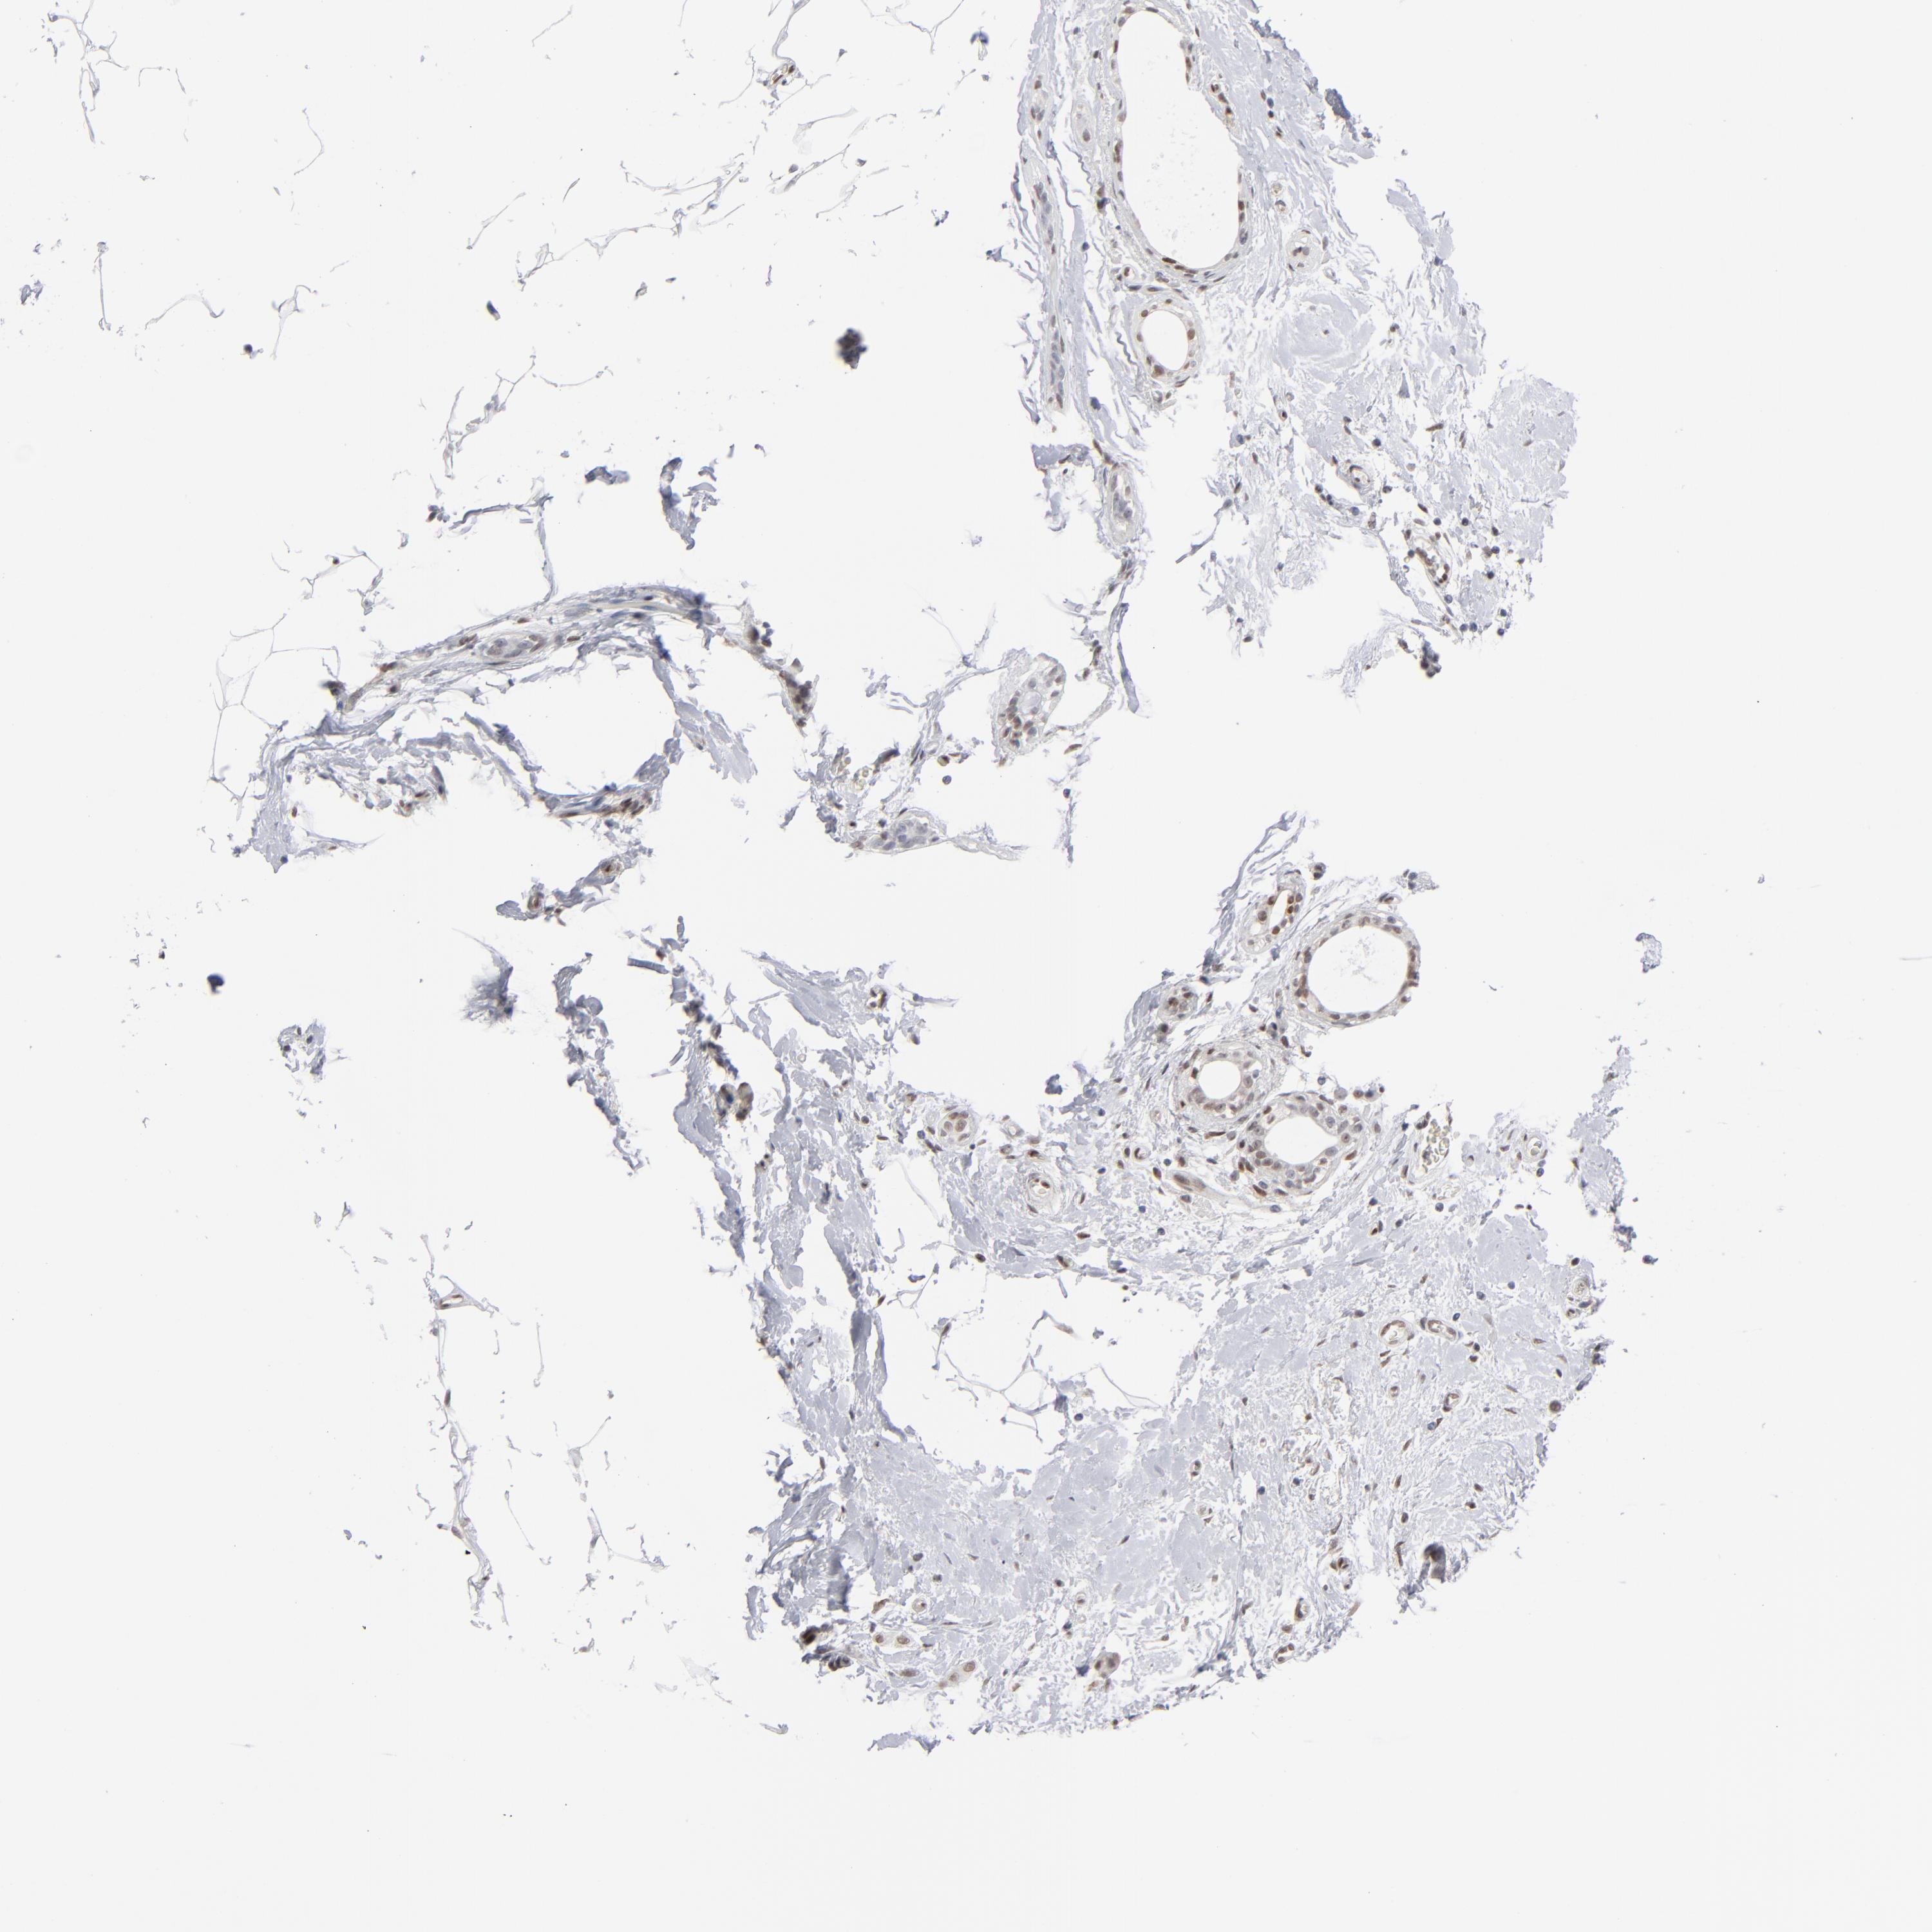

CANCER BREAST CANCER Show tissue menu

BRCA TCGA BRCA VALIDATION PROTEIN EXPRESSION